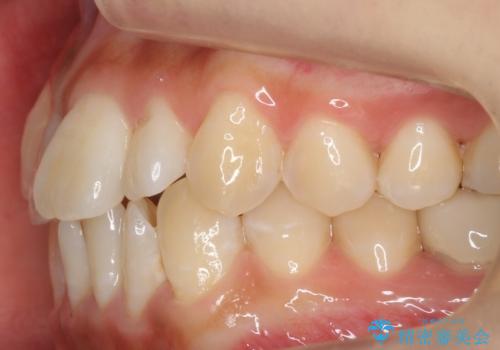

八重歯 インビザラインで抜歯矯正 ただし1本のみの抜歯で済みます

今回は口元も出ていないうえに、右上のみの八重歯のため奥歯を後ろに下げて治療しました。

右上の犬歯をおろしてくるのに、顎間ゴムを使用しています。